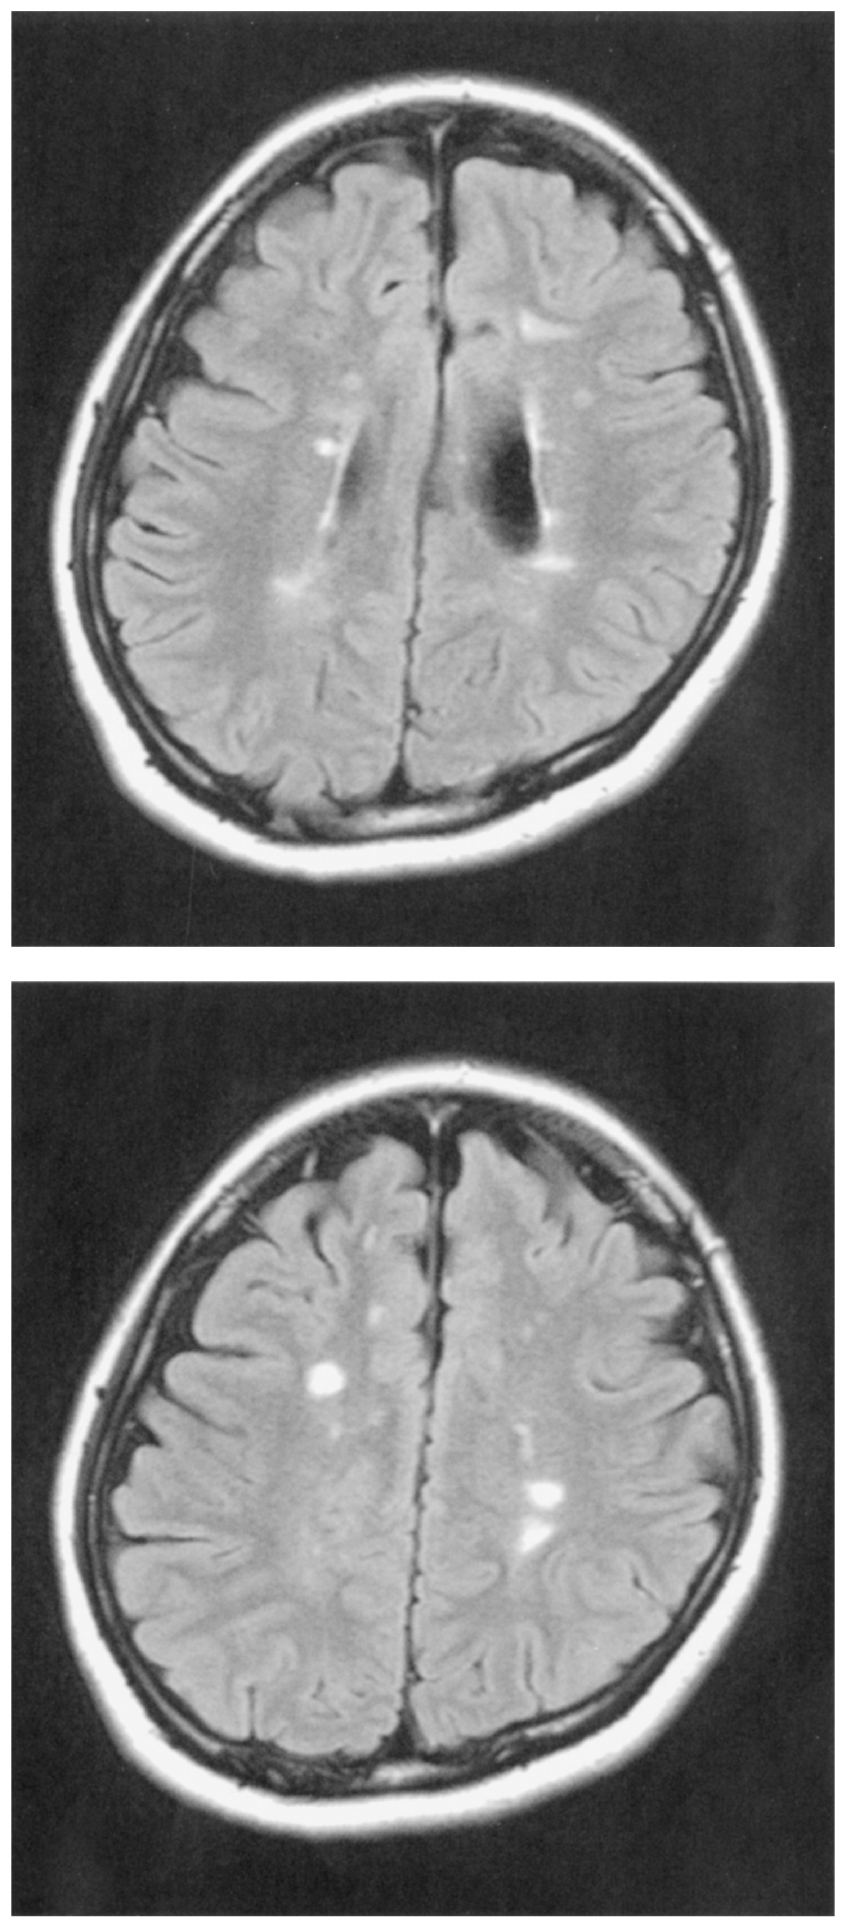

頭部単純MRIのFLAIR像を下に示す。同時に行われた頭部造影MRIでは異常な造影効果を認めた。